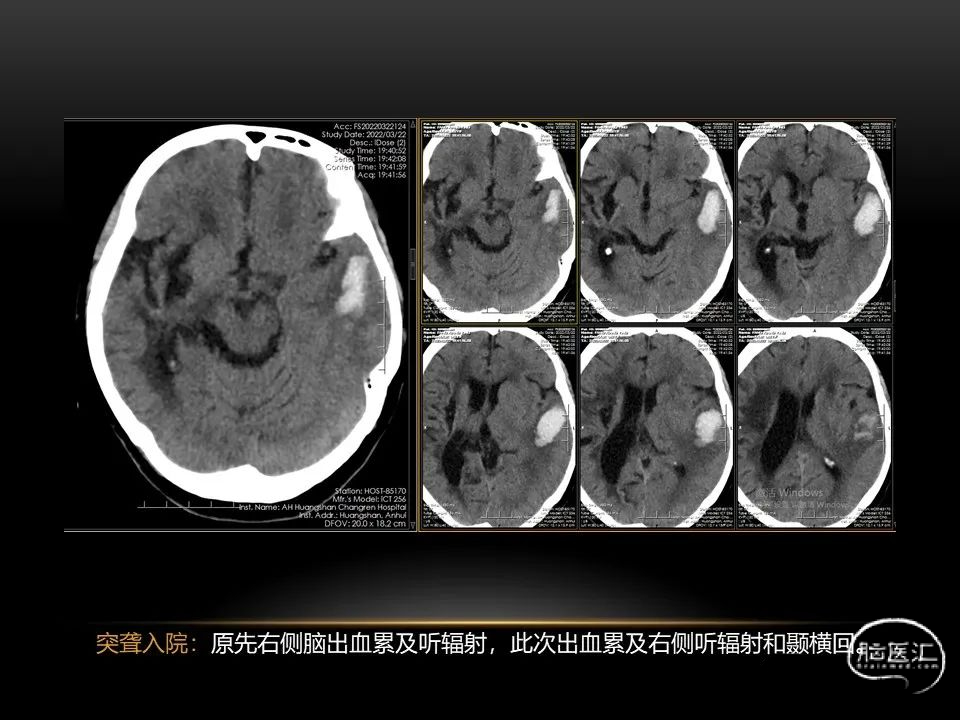

自发性脑出血不仅仅累及内囊后肢才会出现偏瘫及偏身感觉障碍,病变累及大脑脚或辐射冠同样有可能有类似症状和体征。内囊、辐射冠、大脑脚等结构之间是延续的,只是不同区域不同名称而已。定位诊断需要对解剖结构概念清晰,读片准确辨认,灵活掌握。